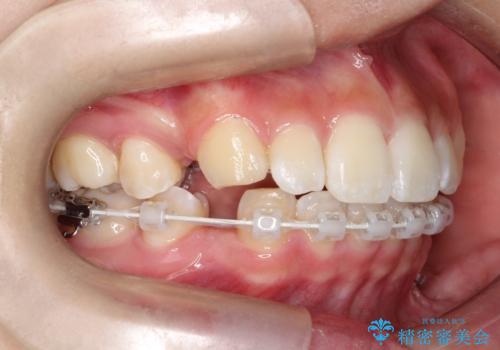

- ハーフリンガル

目立たない装置が希望とのことでハーフリンガルで治療をすることとしました。

当院では裏側矯正という方法も提供しています。裏側矯正は、装置を歯の裏側に取り付けるため、外側からは目立ちにくくなります。この治療法は、見た目に気を使いたい方に特におすすめです。